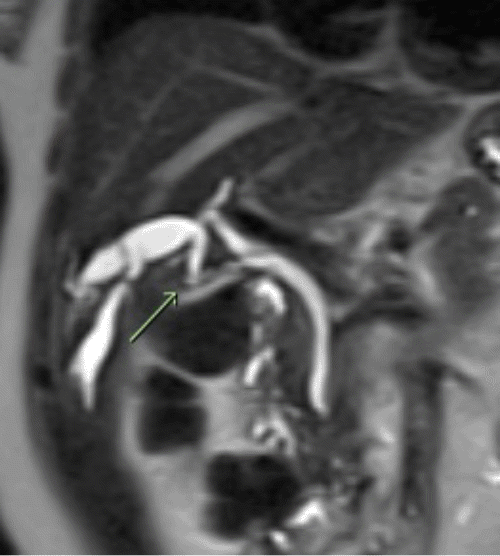

The final examination of the surgical pathology demonstrated chronic cholecystitis with cholelithiasis. Due to potential malignancy concerns within the intrahepatic choledochal cyst, a magnetic resonance cholangiopancreatography (MRCP) was performed two months following the cholecystectomy. This subsequent imaging revealed an anomalous finding—a fusiform dilatation of a specific right intrahepatic duct. This dilated duct drained a portion of segments 4B and 5 directly into the remnant of the cystic duct (Figures 1B and 1C). Notably, to the authors' knowledge, this is the first documented instance of such anomalous drainage of an intrahepatic choledochal cyst. The patient remained free of biliary symptoms one year after the index operation.

C) MRCP demonstrates dilated intrahepatic ducts draining segments 4B and 5 (IH 4B/5) into the remnant of the cystic duct (R-CD) following cholecystectomy.